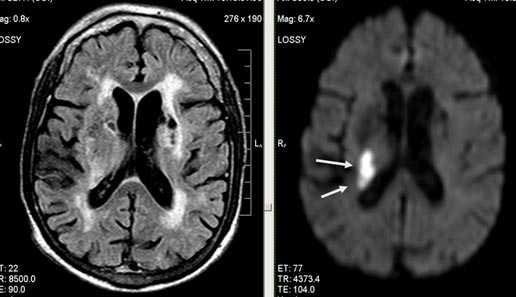

Выраженная сосудистая энцефалопатия с наличием множественных очагов хронической ишемии, лакунарных постишемических кист. Программа ДВИ четко показывает фокус острого ОНМК в базальных ядрах справа на фоне лейкодистрофии.